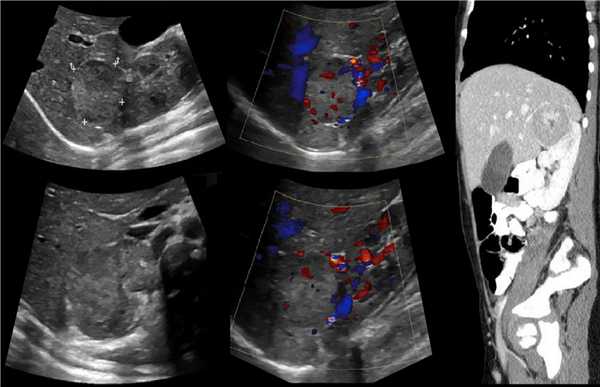

На УЗИ в мочевом пузыре или в уретре определяется анэхогенное образование, округлой формы, с четким и ровным контуром; соответствующий мочеточник обычно заметно расширен; может присутствовать гидронефроз верхней части удвоенной почки. Уретероцеле определяют как внутрипузырные (полностью внутри мочевого пузыря) или внепузырные (некоторая часть постоянно расположена в шейке мочевого пузыря или в уретре).

Рисунок. На УЗИ определяется удвоенная чашечно-лоханочная система, расширена лоханка верхнего сегмента (1) и мочеточник на всем протяжение (2, 3), в мочевом пузыре уретроцеле (4). Полное или неполное удвоение чашечно-лоханочной системы возможно увидеть с помощью КТ-урографии.

Рисунок. Дистальный отдел мочеточника расширен, в мочевом пузыре анэхогенное образование с тонким и ровным контуром — уретероцеле.

Рисунок. Двустороннее уретероцеле на УЗИ: в режиме ЦДК из верхушек уретероцеле определяется выброс мочи.

Если обнаружили гидронефроз верхнего сегмента удвоенной почки, должно поискать расширенный мочеточник и уретероцеле.

Иногда расширенный мочеточник или гипоэхогенная матка приподнимают задне-нижнюю стенку мочевого пузыря, тогда ошибочно диагностируют уретероцеле. Обратите внимание, уретероцеле отделено от просвета мочевого пузыря тонкой мембраной, а псевдоуретероцеле — толстой стенкой.